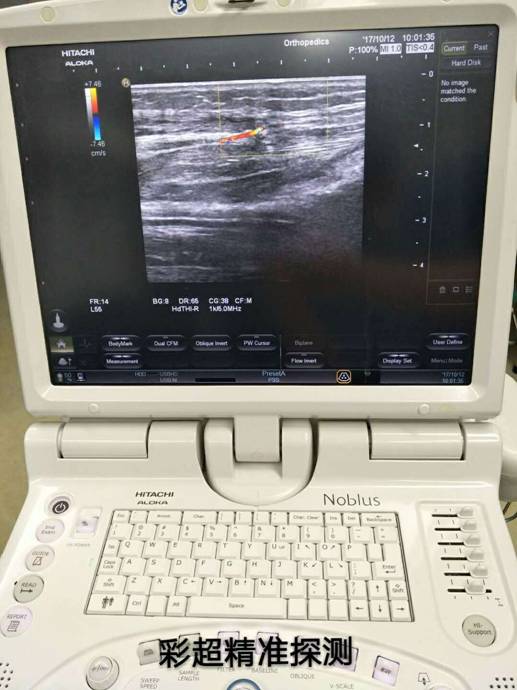

彩超定位精準(zhǔn)治療骨折修復(fù)皮瓣

訊員萬忠波、陳平國報(bào)道:粉碎性骨折+皮膚軟組織缺損+骨(肌腱)外露等損傷有了新療法,衡陽市中心醫(yī)院采用彩超精準(zhǔn)定位、多學(xué)科協(xié)作施術(shù),實(shí)現(xiàn)“大手術(shù)小創(chuàng)傷”。

近一個(gè)月來,衡陽市中心醫(yī)院收治了多位外傷導(dǎo)致小腿多處粉碎性骨折,小腿部分皮膚軟組織缺損、骨(肌腱)外露的患者,醫(yī)院燒傷整形科、骨科、超聲科多科協(xié)作,通過施行彩超定位下,小腿穿支皮瓣轉(zhuǎn)移修復(fù)創(chuàng)面手術(shù),均取得良好的手術(shù)效果,極大地減輕了患者的疼痛和創(chuàng)傷。

骨科根據(jù)患者骨折情況分別施行骨折復(fù)位+內(nèi)(外)固定術(shù),然后由燒傷整形科根據(jù)患者皮膚軟組織缺損情況,制定小腿穿支皮瓣轉(zhuǎn)移修復(fù)創(chuàng)面方案。為保證手術(shù)成功率,燒傷整形科會(huì)同超聲科由黃道遠(yuǎn)主任于術(shù)前利用彩超精準(zhǔn)的探測小腿術(shù)區(qū)的各個(gè)動(dòng)脈穿刺,并逐一標(biāo)記,再由燒傷整形科手術(shù)團(tuán)隊(duì)根據(jù)動(dòng)脈穿支的分布情況設(shè)計(jì)皮瓣,施行小腿穿支皮瓣轉(zhuǎn)移修復(fù)術(shù)。

由于采用了彩超定位技術(shù),使得皮瓣設(shè)計(jì)方案更合理,手術(shù)操作更精準(zhǔn),手術(shù)耗時(shí)更少,更因?yàn)楸Wo(hù)好了血管,術(shù)后皮瓣腫脹,存活均較以往有明顯改善,手術(shù)效果得到極大保障,患者滿意度大大提高。